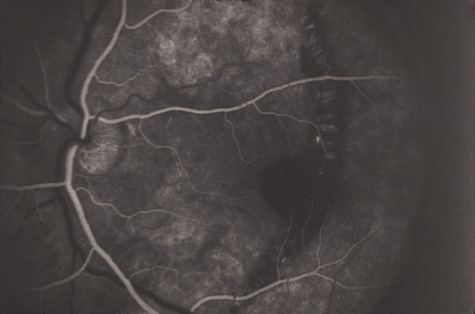

COMMOTIO RETINAE

Commotio retinae (Latin, meaning retinal contusion) is a contrecoup injury. It can occur peripherally (Fig. 8) or centrally, in which case it is called Berlin's edema (Fig. 9). Immediately and for several hours after the trauma, the retina appears normal, although the patient may complain of decreased vision. Thereafter, the outer layers of affected retina become opaque. On fluorescein angiography, the opaque retina blocks background choroidal fluorescence, and in most cases there is no leakage into or under the retina (Fig. 10). For years, clinicians had difficulty explaining this blockage, because leakage is expected in conditions with edema. It was then shown in experimental animals and in human autopsy eyes that Berlin's edema is not true edema. The retinal opaqueness is the result of intracellular edema and fragmentation of the photoreceptor outer segments and intracellular edema of the underlying pigment epithelium. There is little or no intercellular fluid.66–69

Fig. 10. A: Commotio retinae in the macula. B: On the angiogram there is no leakage in the area of commotio retinae.

The visual acuity in commotio retinae varies from 20/20 to 20/400 and does not always correlate with the degree of retinal opacification. There is no known treatment. The prognosis is usually excellent except in cases with associated subfoveolar choroidal rupture and in cases with choroidal rupture with subfoveolar hemorrhage. Poor visual recovery can also be expected in cases with severe retinal pigment epithelial damage. Serous retinal detachment (Fig. 11) signals this condition, which can be confirmed by leakage of fluorescein into the subretinal space.70